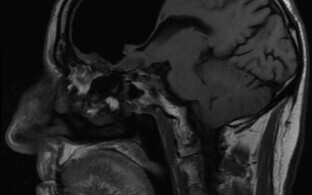

Naksuvat ja kriipivat heli kuulsid ka arstid. Pealiskaudsel vaatlusel olid pääsenud õhumullid sügavamatesse kudedesse. Neid leidus kaela ülaosast kuni rinnakorvini välja. Oletusi kinnitasid kompuuterotomograafiga tehtud ülesvõtted.